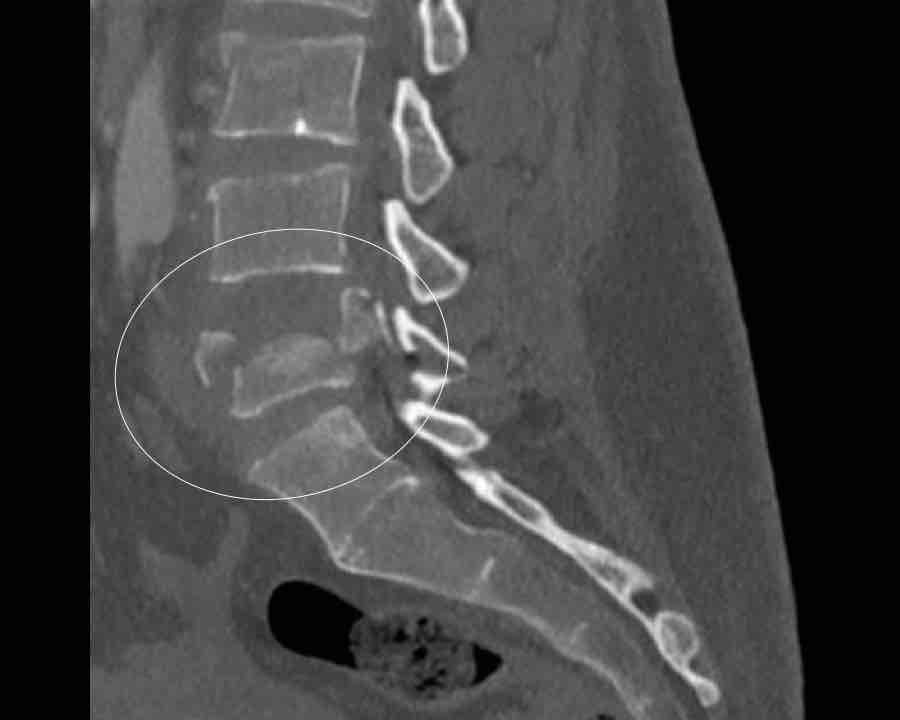

Findings

- The most severe level is L4/5 with dislocation (dotted lines)

- Facet fractures at L4 (arrows).

- A4 burst fracture (circle).

Conclusion:

Injury type C + A4 at L4/5.